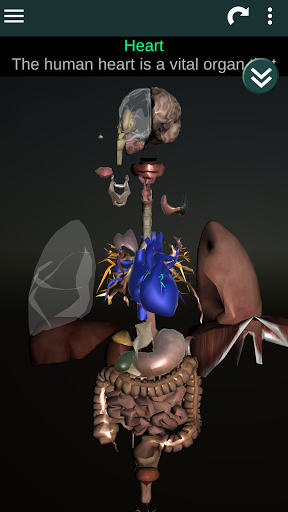

Показує 3D анатомічну модель основні органи людського тіла та опис кожного з них.

* Серце, що включає передсердя, шлуночки, аорту і одушевлення цього органу.

* Легкий доступ і навігація (масштабування, 3D-обертання).

* Описи кожного органу.